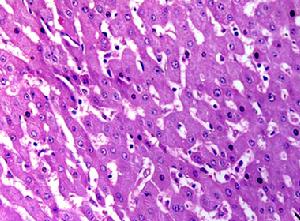

假性甲狀旁腺功能減退症

(三)假性甲狀旁腺功能減退症如假性甲狀旁腺功能減退症Ia、Ib型和Ⅱ型、以及假-假性甲狀旁腺功能減退症(pseudopseudohypoparathyroidism)。